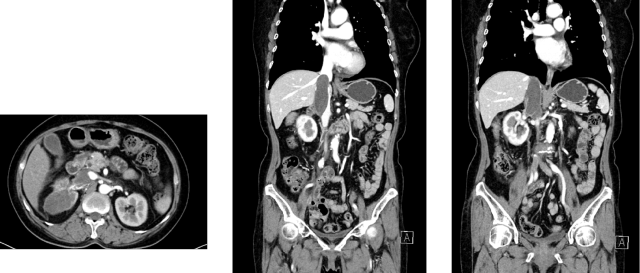

<p><strong>摘要</strong></p><p>女性，64 岁<br/>主诉：血尿1周，检查发现右肾肿瘤，于 2023-06-17 就诊于我科<br/>查体：浅表淋巴结未触及肿大，心、肺、腹（-）<br/>ECOG 评分：1 分<br/>既往史：子宫肌瘤术后 20 年；神经衰弱病史 1 年，佐匹克隆治疗；高血压病史 20 年，硝苯地平、利血平治疗。</p><p><strong><br/></strong></p><p><strong>临床资料</strong></p><p>一、辅助检查</p><p>肾脏 MR 平扫＋动态增强：右肾中上份为主见类椭圆形等 T1 等 T2 信号肿物，截面约 8.0×6.5cm，T1WI 反相位部分区域信号强度减低，DWI 及 ADC 扩散受限，呈不均匀快进快出强化模式；病灶侵及部分右肾静脉-下腔静脉，以上水平下腔静脉全程粗大，可见团状不均匀强化充盈缺损，肝中静脉内见条状充盈缺损区，符合右肾恶性肿瘤（CCRCC 可能大）累及部分右肾静脉并下腔静脉瘤栓，肝中静脉栓子形成 MR 表现。</p><p>病理：2023-06-19 行右肾穿刺活检术：（右肾占位穿刺）符合透明细胞性肾细胞癌。 免疫组化：CA9（+），Vimentin（+），CK7（-），TFE3（-），FH（+），PAX8（+），CD117（-）。</p><p>2023-06-14 泌尿系 CTU 增强：右肾及下腔静脉内富血供肿块，右肾癌并腔静脉癌栓达膈肌以上，肾占位最大横截面 9.9*6.1cm，腔静脉占位最大横截面 6.1cm，上下范围 12.4cm，可见肝静脉栓子。</p><p style="text-align: center;"><img src="https://img1.dxycdn.com/p/s10/2025/1124/477/6332268857029482991.png!w640" alt="图片1.png"/></p><p>二、诊断与鉴别诊断</p><p>初步诊断：右肾透明细胞癌并腔静脉瘤栓；肝静脉癌栓</p><p>分期：cT3bN0M0</p><p><br/></p><p><strong>治疗情况</strong></p><p>2024-09-13 ： 胸部+全腹部(含盆腔）CT 平扫+增强 ：右肾中上份见一类椭圆形略低密度灶，较大截面约 5.5×4.0cm，边界欠清，增强扫描呈欠均匀轻度强化，较前增大，病灶侵及部分右肾静脉-下腔静脉，以上水平下腔静脉全程粗大，较宽处约 3.8cm。右肾恶性肿瘤并右肾静脉、下腔静脉治疗后 CT 所见。</p><p>2024-11-01： 胸部+全腹部(含盆腔）CT 平扫+增强 ：右肾中上份见一类椭圆形略低密度灶，较大截面约 5.5×4.0cm，边界欠清，增强扫描呈欠均匀轻度强化，较前变化不明显，病灶侵及部分右肾静脉-下腔静脉，以上水平下腔静脉全程粗大，较宽处约 3.8cm 右肾恶性肿瘤并右肾静脉、下腔静脉治疗后CT所见，较前变化不明显 SD。<br/>胃肠道反应较重，恶心纳差乏力伴声音嘶哑反应较重，高血压，AE3 级。</p><p>2024-11-01：再次换用舒尼替尼 50mg，2-1 方案；<br/>消化道不良反应较重，恶心呕吐重，1 周内住院两次，AE3 级。</p><p>2024-11-15：换伏罗尼布 200mg po qd+艾帕洛利托沃瑞利单抗注射液。</p><p>2024-09-13：</p><p style="text-align: center;"><img src="https://img1.dxycdn.com/p/s10/2025/1124/538/0650772702832582991.png!w640" alt="图片2.png"/></p><p>2024-11-01：</p><p style="text-align: center;"><img src="https://img1.dxycdn.com/p/s10/2025/1124/788/4220497517252582991.png!w640" alt="图片3.png"/></p><p>2024-11 至今：伏罗尼布 200mg po qd+ 艾托组合抗体</p><p>CT复查：2025-02-07，胸部+全腹部(含盆腔）CT 平扫+增强 ：右肾中上份见一类椭圆形略低密度灶，较大截面约 4.6×3.8cm，边界欠清，增强扫描呈欠均匀轻度强化，较前变化不明显，病灶侵及部分右肾静脉-下腔静脉，以上水平下腔静脉粗大，较宽处约 3.8cm，右肾恶性肿瘤并右肾静脉、下腔静脉癌栓治疗后 CT 所见，癌栓位于膈肌下 2cm，肝静脉癌栓消失（PR）。</p><p>AE：irAE 甲状腺功能减退（对症治疗效果好）；肝功轻度异常；未见其他明显不良反应。</p><p><img src="https://img1.dxycdn.com/p/s10/2025/1124/146/8258361971504582991.png!w640" alt="图片5.png"/></p><p><img src="https://img1.dxycdn.com/p/s10/2025/1124/089/4646237200034582991.png!w640" alt="图片6.png"/></p><p><br/></p><p><strong>病例1：新辅助可能性讨论</strong></p><p>肾癌新辅助治疗的手术获益：从不可切除到部分切除的转变。</p><p>场景一：不可切除的肿瘤变得可以切除（癌栓等）</p><ol class=" list-paddingleft-2" style="list-style-type: decimal;"><li><p>巨大、复杂，侵犯肾蒂血管，淋巴结融合成团，高级别腔静脉瘤栓，周围重要器官受侵犯，手术风险高；</p></li><li><p>新辅助治疗有助于瘤栓降级、降低手术难度；合并癌栓的肾癌选择应用新辅助治疗为无法手术的患者再次赢得手术机会。</p></li></ol><p>场景二：不可部分切的肿瘤变得可以部分切除（保肾、高难度保肾）</p><ol class=" list-paddingleft-2" style="list-style-type: decimal;"><li><p>在控制切缘阳性率的同时尽可能保肾；保留肾单位手术（PN）结合使用时增强肾脏功能保留，这对于局部晚期RCC的治疗至关重要；</p></li><li><p>通过术前新辅助治疗，可以使肿瘤体积缩小，增加手术切除的成功率，提高肾癌患者的生存率，帮助双侧肾癌及孤立肾患者行保留肾单位手术或行根治性切除术。</p></li></ol><p>其他优势</p><ol class=" list-paddingleft-2" style="list-style-type: decimal;"><li><p>测试药物敏感度，为晚期阶段系统治疗药物选择提供参考；</p></li><li><p>调节免疫微环境，增加免疫反应，改善免疫抑制的肿瘤微环境。</p></li></ol><p>专家共识建议：减少因为不良反应而中断治疗的比例，更有益于患者的生存获益与生命质量的提高。</p><p><img src="https://img1.dxycdn.com/p/s10/2025/1124/709/8041462239455582991.png!w640" alt="图片7.png"/></p><ul class=" list-paddingleft-2" style="list-style-type: disc;"><li><p>靶向药物治疗肾癌时不良反应的管理非常重要。减少因为不良反应而中断治疗的比例更有益于患者的生存获益与生命质量的提高。</p></li><li><p>若出现 Ⅲ 级皮肤症状（重度皮肤改变，伴疼痛，影响个人日常生活），则应中止靶向治疗 1～2 周，必要时请皮肤科会诊，改善皮肤症状恢复至 0～I 级，方可考虑恢复靶向药物的使用。</p></li><li><p>转氨酶&gt;3×ULN 和总胆红素&gt;2×ULN 应停止治疗，且对患者持续进行监测，直至氨基转移酶恢复至1级或基线；若转氨酶水平&gt;8×ULN 应立即停止治疗，纠正肝功能后考虑其他靶向药物。若转氨酶水平＞8×ULN 应立即停止 治疗，纠正肝功能后考虑其他靶向药物。</p></li></ul><p><strong><br/></strong></p><p><strong>伏罗尼布--首个拥有中国自主知识产权肾癌小分子靶向自主创新药</strong></p><p>亲和力高：分子结构设计上，通过引入二甲胺基甲酰基（C=O）与 VEGFR 形成额外氢键，引入S-构型吡咯烷基分子构型固定，增加靶点亲和力。</p><p>组织蓄积毒性低：「二甲胺基甲酰基」碱性降低，降低了磷脂生物膜的穿透性，降低了组织分布，避免了组织蓄积毒性。</p><p>易代谢：「二甲胺基甲酰基吡咯烷基」具有更多的体内代谢位点，伏罗尼布和其 N-脱甲基代谢产物 X-297 具有更快的体内清除速率，消除相半衰期更短，可实现靶点的间歇抑制，降低毒性。</p><p><strong><br/></strong></p><p><strong>伏罗尼布单药——安全性良好，患者更易耐受</strong></p><p><img src="https://img1.dxycdn.com/p/s10/2025/1124/152/4872430269666582991.png!w640" alt="图片8.png"/></p><p><strong><br/></strong></p><p><strong>小结</strong></p><p>1、晚期肾癌进入靶免治疗时代，但靶向治疗依旧是重要的选择；无论靶向还是靶免一线治疗，药物不耐受普遍存在。中国回顾性研究发现，约 24.6% 的患者因无法耐受不良反应终止一线治疗。</p><p>2、伏罗尼布是中国肾癌治疗领域首个具有中国自主知识产权的创新药物，具有更强的靶点亲和力，毒性更小，组织蓄积性更低。</p>              ]]>